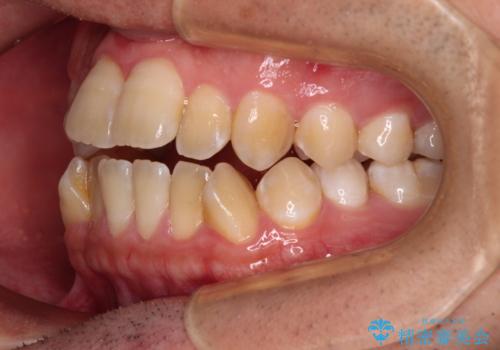

オープンバイトをインビザラインで矯正治療

- 前歯の開咬を気にして来院された患者様です。

開咬の治療は、前歯を閉じるように動かすとともに、上下臼歯を圧下(骨内にめり込ませる)させることで進めて行きます。

インビザラインは臼歯の圧下を効果的に行えるため、インビザラインを用いて矯正治療を行うこととしました。